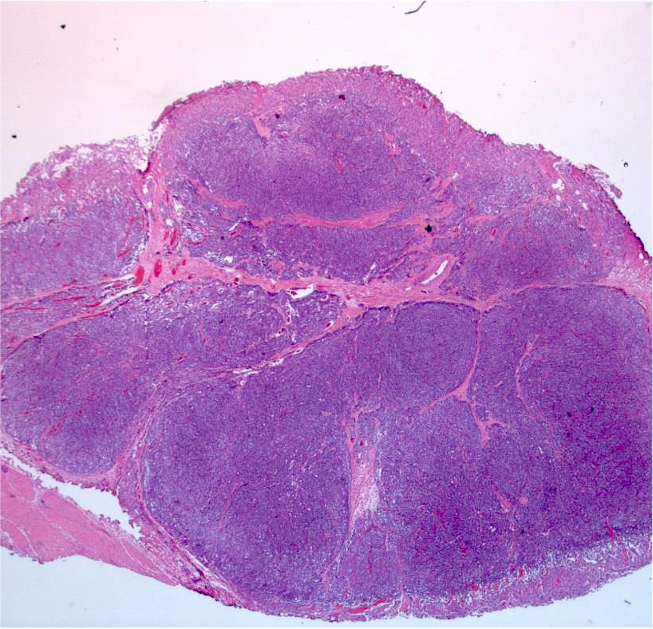

Microscopic (histologic) description

- Typical morphology: epithelioid cells with abundant, eosinophilic / amphophilic, granular cytoplasm and round / ovoid, vesicular / salt and pepper nuclei, arranged in a nested / zellballen pattern and separated by fibrovascular septae with sustentacular cells (Am J Surg Pathol 2004;28:94, World J Clin Cases 2014;2:591, Endocr Pathol 2022;33:90)

- May have focal pleomorphism, nuclear hyperchromasia, low mitotic activity or clear cytoplasm

Microscopic (histologic) images

Contributed by Theodorus H. van der Kwast, M.D., Ph.D., Michelle R. Downes, M.D., Debra L. Zynger, M.D. and David Cohen, M.B.B.Ch., M.D.